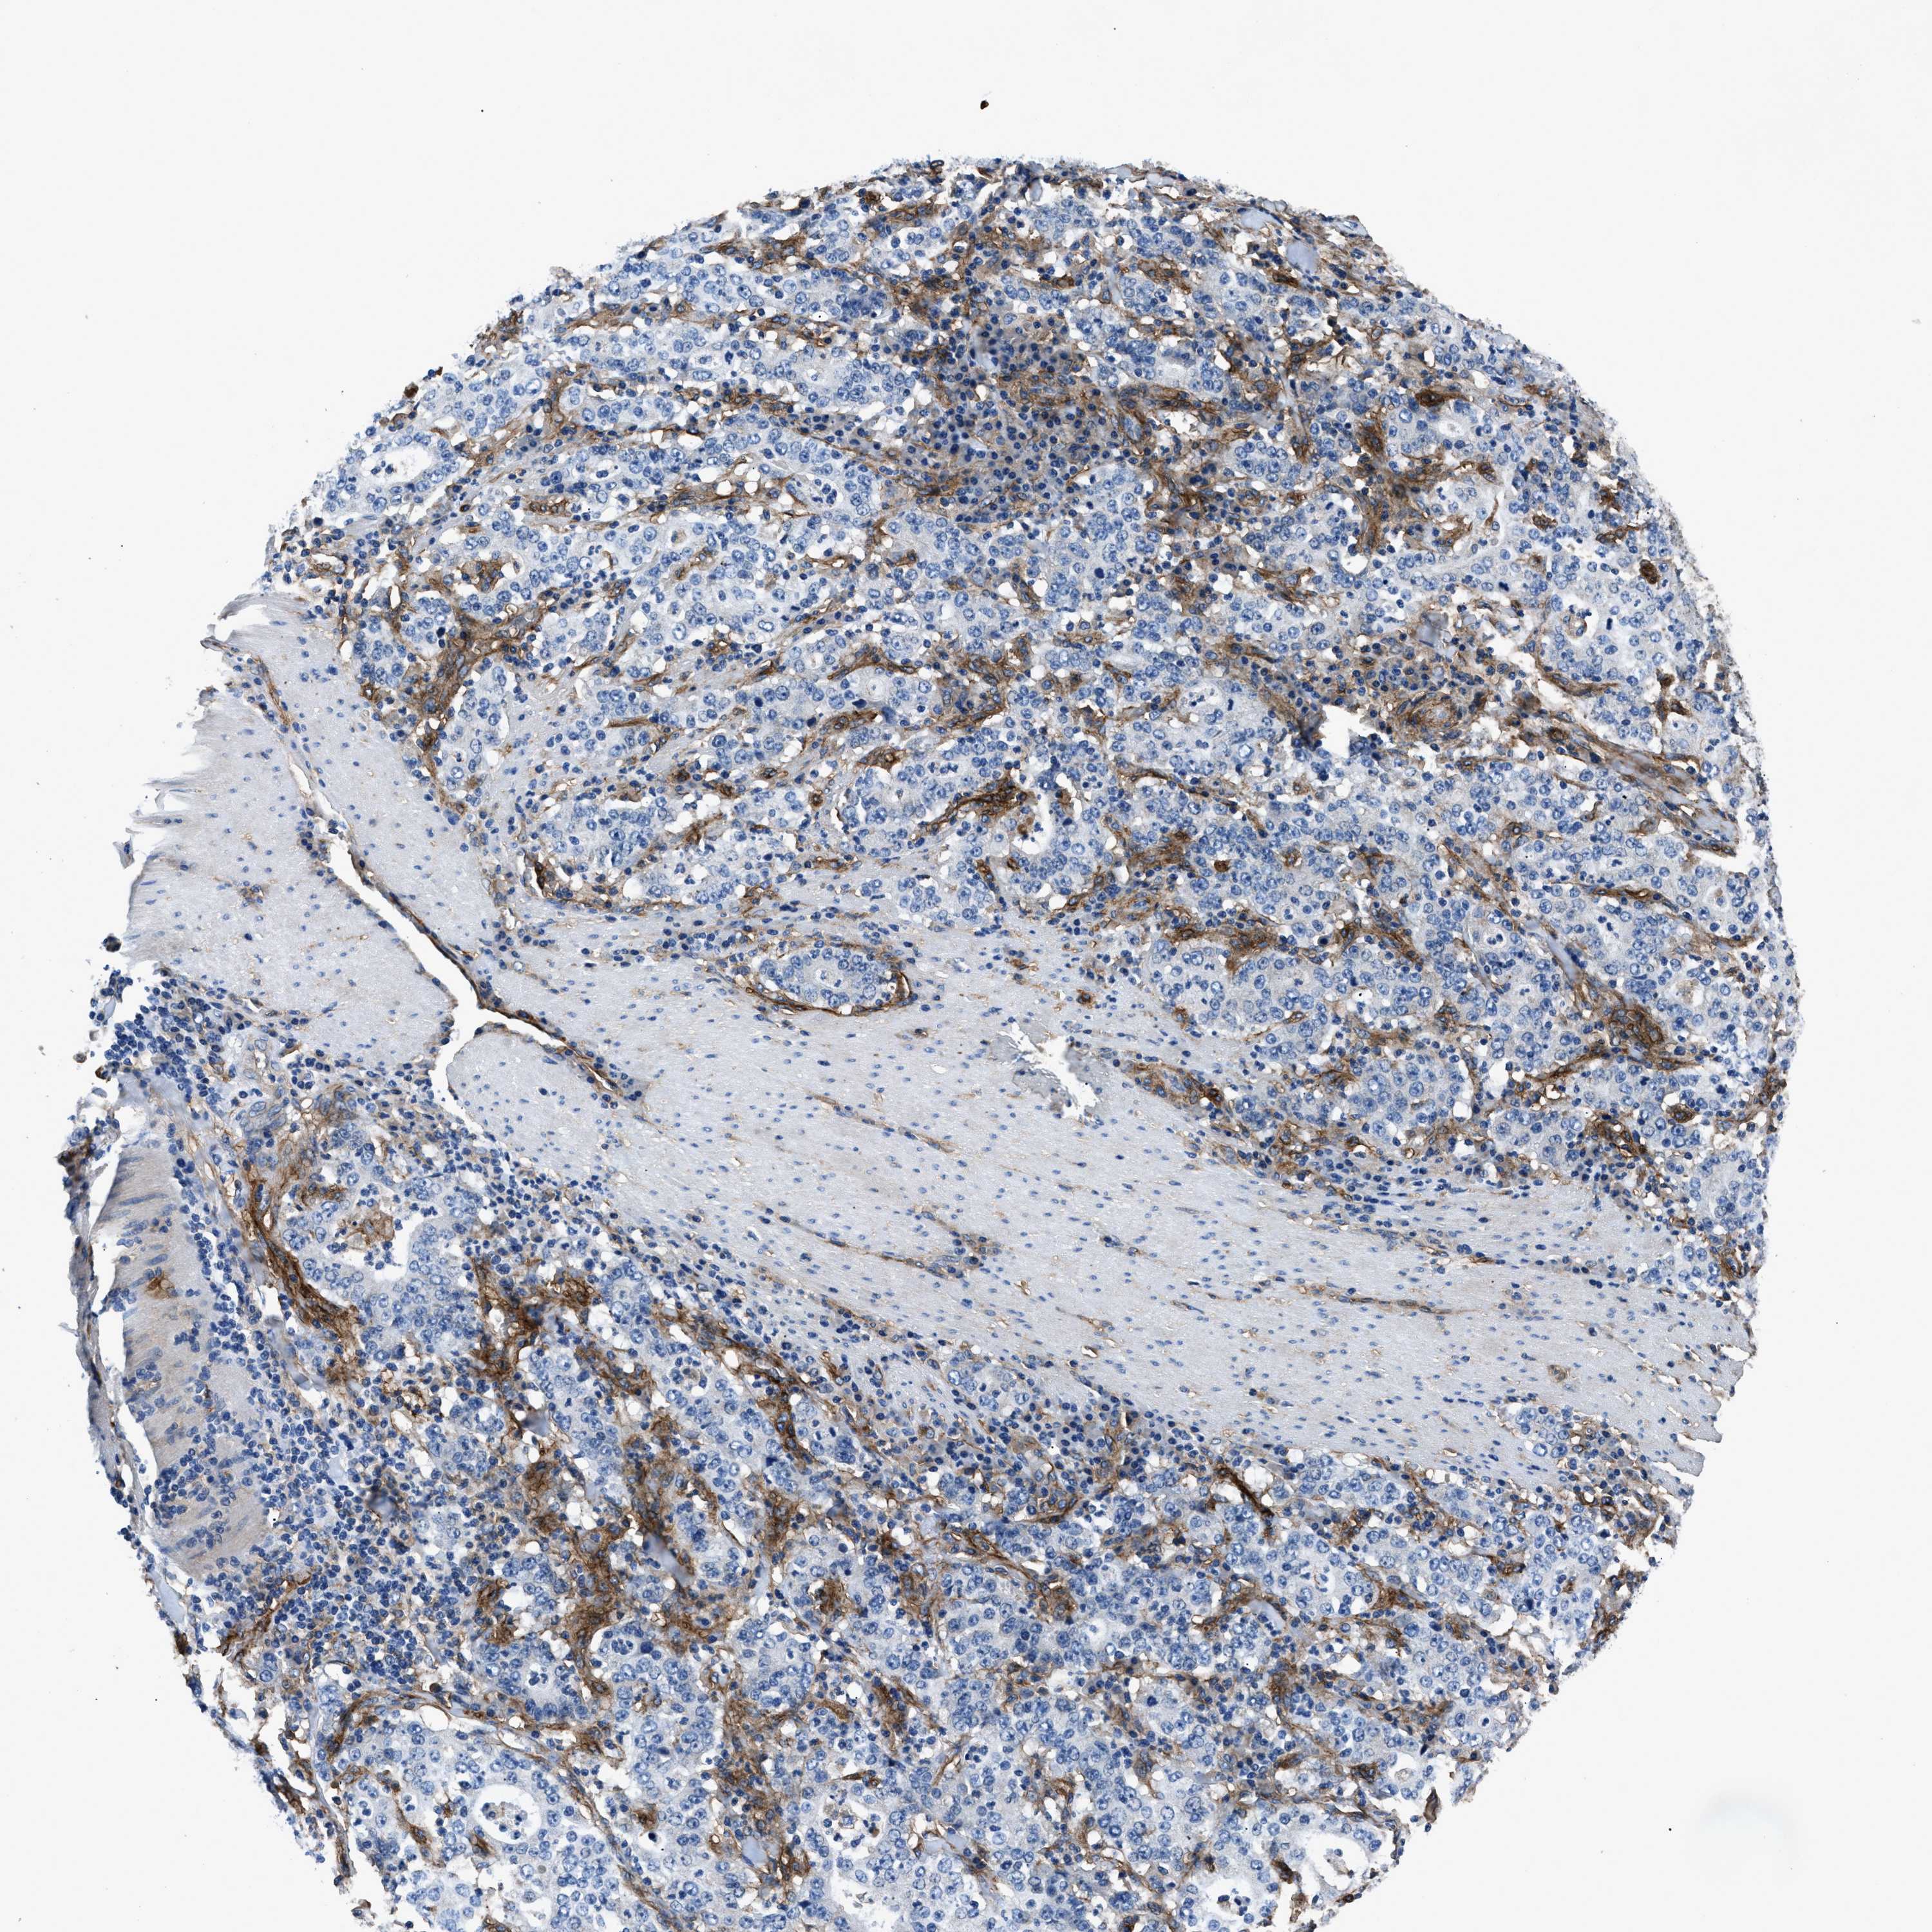

STOMACH CANCER - Protein expressioni

A mouse-over function shows sample information and annotation data. Click on an image to view it in a full screen mode. Samples can be filtered based on level of antibody staining by selecting one or several of the following categories: high, medium, low and not detected. The assay and annotation is described here.

Antibody stainingi

Antibody staining in the annotated cell types in the current human tissue is reported as not detected, low, medium, or high, based on conventional immunohistochemistry profiling in selected tissues. This score is based on the combination of the staining intensity and fraction of stained cells.

Each image is clickable and will lead to virtual microscopy that enables deeper exploration of all samples and also displays staining intensity scores, fraction scores and subcellular localization as well as patient and tissue information for each sample.

Antibody HPA009285

Antibody HPA017139

Antibody CAB017826

Staining

High

Medium

Low

Not detected

Intensity

Strong

Moderate

Weak

Negative

Quantity

>75%

75%-25%

<25%

None

Location

Nuclear

Cytoplasmic/membranous

Cytoplasmic/membranous,nuclear

Adenocarcinoma, NOS

Adenocarcinoma, High grade